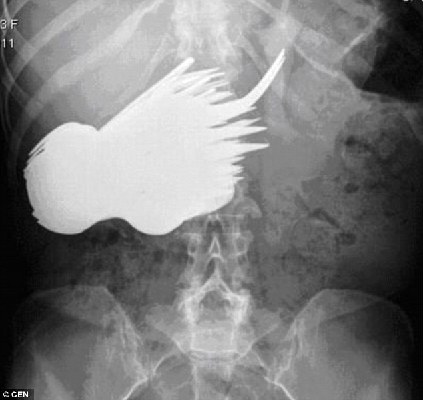

X光片顯示,瑪格麗特的胃里有很多餐具。

中國(guó)日?qǐng)?bào)網(wǎng)環(huán)球在線消息:英國(guó)《每日郵報(bào)》28日披露,30年前,荷蘭女子瑪格麗特·達(dá)阿爾瑪因?yàn)槲竿措y忍,到鹿特丹一家醫(yī)院檢查。診斷結(jié)果令人瞠目結(jié)舌:瑪格麗特的胃里竟然有78把銀制勺子和叉子。這段奇聞?shì)W事直到最近才被德國(guó)一家醫(yī)學(xué)雜志曝光。

根據(jù)德國(guó)醫(yī)學(xué)雜志《精神病在線雜志》的披露,30年前,年僅22歲的瑪格麗特被查出胃里竟然有78把餐具。醫(yī)生立即為她實(shí)施了手術(shù),將胃中的勺子和叉子一個(gè)接一個(gè)地取了出來(lái)。在場(chǎng)的醫(yī)生和護(hù)士十分不解,她為什么會(huì)吞餐具。